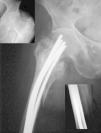

Figura 4. Migración distal con protrusión a través de la piel (imagen pequeña abajo a la izquierda) en una fractura con tan sólo dos clavos, que no rellenaban el canal medular de forma adecuada.

Extracción del material de osteosíntesis

Se realizó la extracción del material de osteosíntesis (AMO) en 55 casos (15%). Cuarenta y cinco pacientes por migración distal con repercusión clínica (fig. 4), 3 pacientes por migración distal asintomática y 7 pacientes por migración proximal sintomática. El tiempo medio hasta la AMO fue de 44 semanas, con dos momentos de máxima incidencia en torno a los 3 meses y al año. En 20 de los 55 casos, las molestias que indicaron la intervención persistieron tras la retirada de los clavos (tabla 1).